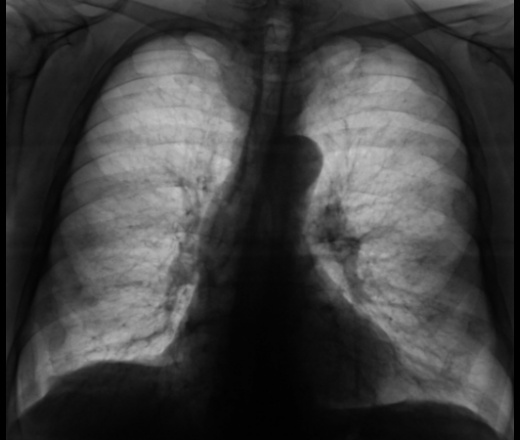

Хм, мне кажется кроме диф. Пневмосклероза (деф.легочной рисунок) и небольшой релпксации правого купода дгмы- ничего серьезного нету. Я бы не придрался (правда я не большой спец пока :)

Пневмосклероз.Эмфизема.Консолидированные переломы ребер с обеих сторон.Увеличение границ сердечной тени, преимущественно , за счет левых отделов.Аорта уплотнена.Если про поводу верхней доли слева-посмотрите скопически+УЗИ мягких тканей шеи.Возраст не указан, конечно, видно, что человек не совсем молодой-может, сосудистый пучок.

Ну, ладно пневмосклероз, а эмфизема-то почему? Легочный рисунок не обеднен, купола диафрагмы не уплощены.

Интересует, что на верхушке?

Старые плевральные наслоения.

структура ребер смущает, можно немного увеличить чтоб отдифференцировать множественные переломы ребер или все же деструкция

Вы правы, с обеих сторон консолидированные переломы ребер. В ребрах деструкции нет.

"Пощупайте" его за щитовидную железу, то, что он не единожны бит, не исключает у него дифузного зоба с легкой загрудинной распространенностью....

"Щупать", конечно можно, да и "щупали" основательно, и за экраном. Но только на девятке вылазит, то, что справа.

Мужчина плотный, и весьма дородный. Интересующая область полность перекрыта плечевым поясом, по - этому и начали томографировать

Значит без КТ дальше "не уедем"?

КТ в протоколе исследования рекомендована.